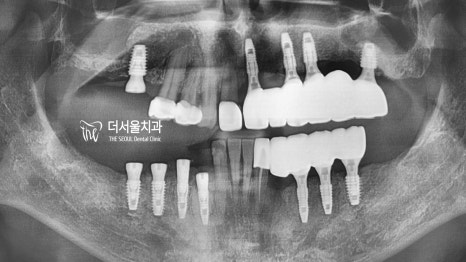

태평역 치과 에서는 꽤 많은 곳을 심어야 되기에

좌,우측 순서를 나누어 진행하기로 했습니다.

『# 20, 30 먼저 완성 후,

# 10, 40을 도와드리기로 했죠.』

우선 상악동과 가까운 곳들은

상악동 거상술을,

치조골이 좋지 않은 곳은

골이식을 동반하기로 하였으며,

살릴 수 있는 몇몇 자연치들은

치주 및 충치치료를 동반하여

기대 수명을 늘려보는 것으로 계획을 세웠습니다.

『어렵고 까다로운 식립 과정』

디지털 분석을 통해

과정 중 유의해야 될 점이나

식립 위치, 방향 등을 결정했습니다.

꽤나 까다로운 과정이기 때문에

정확하고 꼼꼼한 분석을 필요로 하는데요.

분석 상에서도 나와있듯이

골이식을 동반해야 되며,

얇은 치조골의 두께로 drill의

미끌림 또한 주의해야겠네요.

계획했던대로 잘 심어지기만 하면

별다른 문제는 나타나지 않겠지만,

과정이 정말 까다롭고 복잡했습니다.

치조골이 워낙 없었던 분인데다,

잇몸 자체가 좋지 않으셨기에

꽤나 애를 먹었죠.

앞서 계획했던대로 좌측 식립,

크라운 세팅까지 완료한 뒤

우측 과정도 곧장 진행하였습니다.